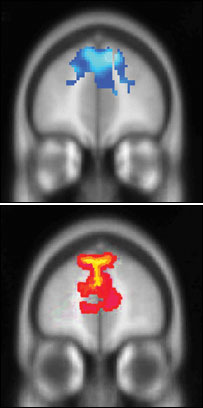

پژوهشگران واکنش ها به خوشحالی( آبی) و ترس( قرمز) را اندازه گرفتند

از مطالعاتی که بر روی تصاوير مغزی افرادی در گروه سنی ۱۲ تا ۷۹ سال به عمل آمده چنين نتيجه گيری شده که بهتر شدن وضعيت ثبات عاطفی و احساسی افراد حتی درهفتمين دهه زندگی شان همچنان ادامه دارد.

پژوهشگران تصاويری را که بيان کننده حالات مختلف احساسی بود به نمايش گذاردند و چنين نتيجه گيری کردند که جوانان ترس را بيشتر و زودتر از خوشحالی تشخيص می دهند.

اين نتايج همچنين مويد اين بود که افراد مسن در واکنش به احساسات منفی بيشتر از جوانان دارای کنترل مغزی اند.